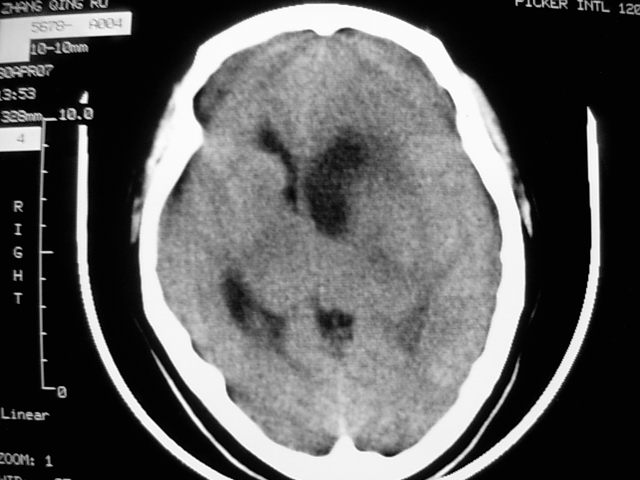

f39y,头疼、眩晕。患者拒绝强化。

左侧脑室增大,前角明显,中线向右移位,左侧脑室内见一肿块,密度不均,1室管膜瘤?2脑囊虫?

左额叶见一巨大椭圆形略低、低密度混杂密度肿块,边界清楚,似与侧脑室额角相通,明显占位效应,左侧侧脑室受压变形,右侧侧脑室扩大,中线结构向右明显弧形移位。鞍上池闭塞。

左侧脑室增大,前角明显,中线向右移位,左侧脑室内见一肿块,密度不均,内见钙化,1室管膜瘤?2脑囊虫?

左侧脑室增大,前角明显,中线向右移位,左侧脑室内见一肿块,密度不均,1室管膜瘤?